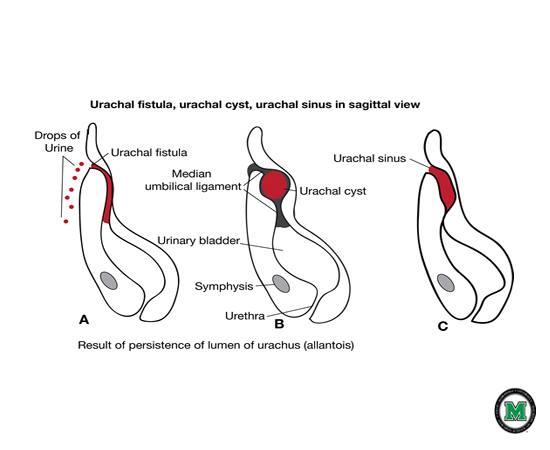

Urachal fistula

Urachal fistula

What is a urichal fistula?

Urachus doesn't close and belly button leaks urin

Urachal cyst

Urachal cyst

what is a Urachus?

a fibrous cord that extends from the umbilicus to the bladder.

Urachal cyst